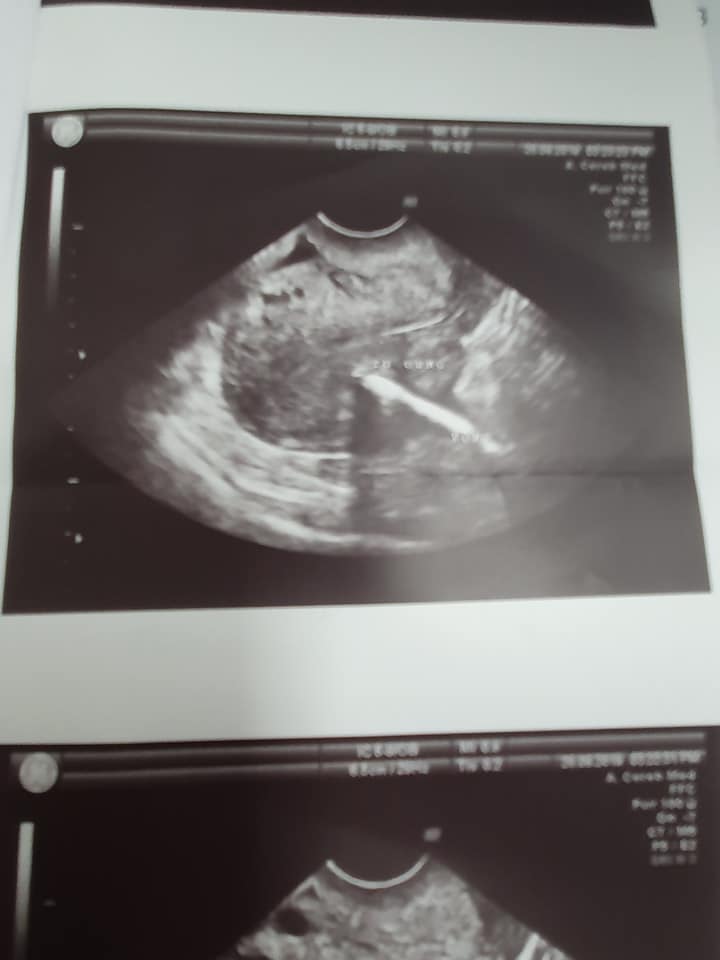

Bệnh nhân 32 tuổi , 3 con, mổ đẻ 3 lần, con thứ 3 3 tuổi, đặt vòng chữ T tránh thai hơn 1 năm. Gần đây thấy đau bụng hạ vị nên đi khám. Khi siêu âm thấy hình ảnh 1 phần cành dọc chữ T nằm trong cơ tử cung. Còn lại cành ngang của vòng nằm trong ổ bụng.

Khi mổ nội soi thấy toàn bộ cành ngang của vòng nằm trong ruột . Mình phải gỡ dính lấy vòng , 1 lỗ thủng nhỏ ở ruột tiến hành khâu lỗ thủng qua nội soi.